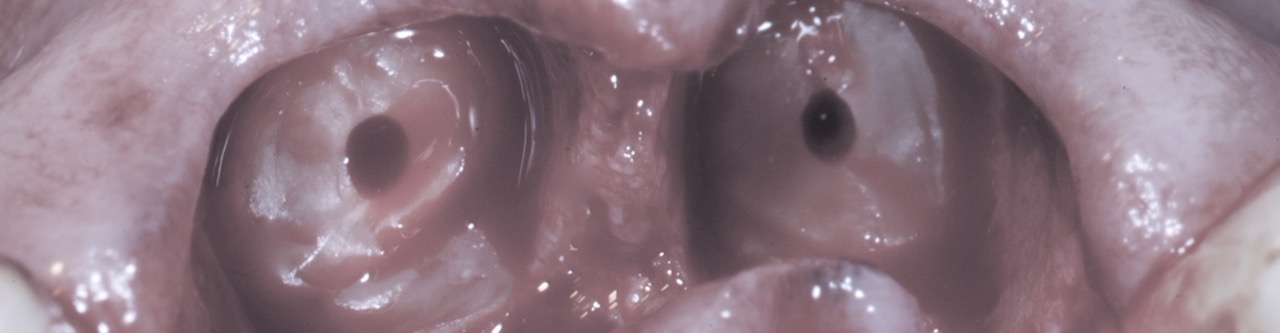

Dental trauma can range from minor enamel injuries to significant loss of teeth and hard and soft tissues. When faced with such emergencies, the clinician must consider surgical, restorative, endodontic and periodontal implications and make quick decisions on a treatment that can lead to the best long-term result. In this presentation, Dr. Kazemi will review various types of dental injuries and a simplified map to choosing the most appropriate treatment quickly and easily. In addition, Dr. Kazemi will discuss complicating factors and treatment concepts.